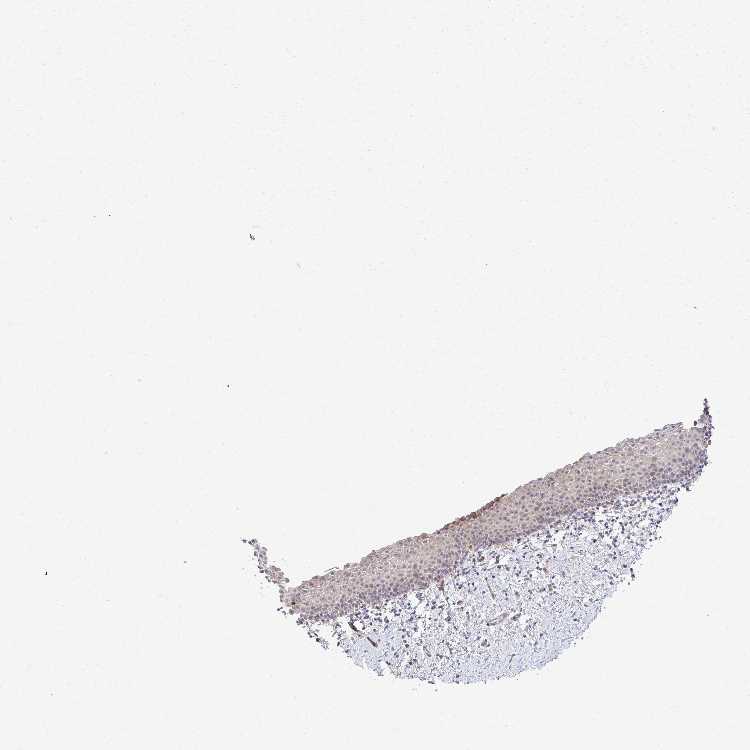

Antibody HPA059235

Squamous epithelial cells Low